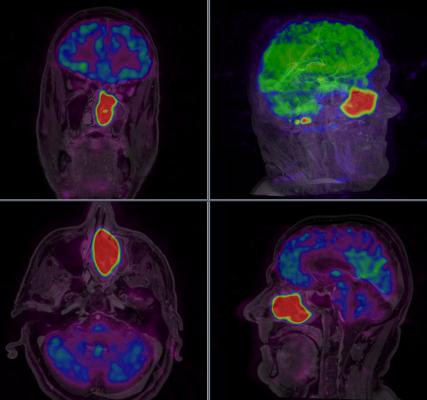

Results of FDOPA PET A C and SRS B E performed in a 56 year